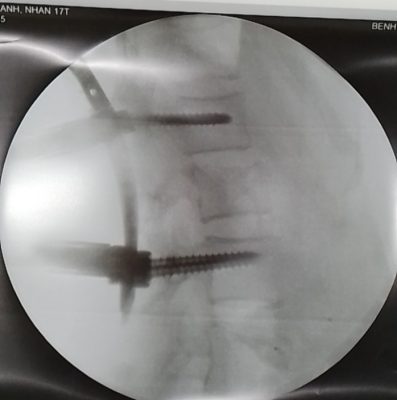

– Sáng ngày 18/1: Kíp phẫu thuật đã tiến hành mổ cố định làm vững cột sống L1-L3 bằng kỹ thuật ít xâm lấn (bắt vít chân cung đốt sống ít xâm lấn qua da).

– Dưới màn huỳnh quang tăng sáng hướng dẫn trong mổ và hệ thống bắt vít ít xâm lấn qua da Sextant thế hệ 2. Ca phẫu thuật thành công sau 60 phút.

Xquang hướng dẫn trong mổ